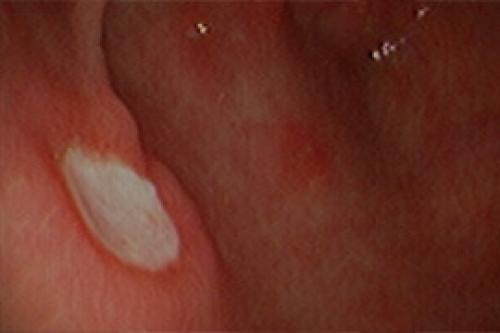

Помимо НР-гастрита и атрофического гастрита (напомним, что данные диагнозы должны быть подтверждены гистологическим исследованием, подробнее в нашей статье «Зачем берут биопсию при гастроскопии?» ) Helicobacter pylori является причиной возникновения эрозивно-язвенных изменений слизистой желудка, двенадцатиперстной кишки и язвенной болезни. Кроме способствования развитию язвы желудка и двенадцатиперстной кишки, наличие НР-инфекции повышает риск желудочно-кишечного кровотечения. Лечение Helicobacter pylori снижает риски кровотечения, повторного обострения язвенной болезни и является наиболее эффективным в заживлении язвенного дефекта, чем терапия только кислотоснижающими средствами.